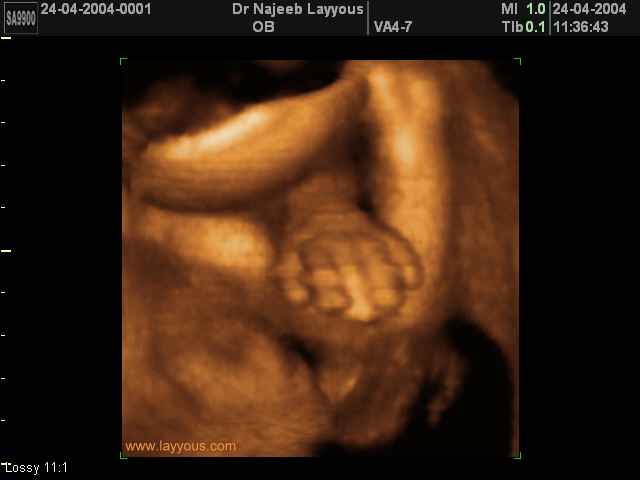

- صور لأطراف الجنين

- صور لتصرفات الجنين داخل الرحم

صور لأطراف الجنين بجهاز الالتراساوند ثلاثي الأبعاد | الدكتور نجيب ليوس